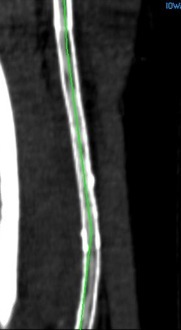

The CTA, particularly with 3D reconstruction, is helpful in planning these cases.

The additional material needed is fluoroscopy and endovascular skills. Directing a subintimal Glidewire helps free the stent and aid passage of the Moll ring dissector.

Adding cold saline seems to help shrink the stents. A plaque free distal end point allow the stents to be removed with a gentle tug.

I put these patients on coumadin anticoagulation. Surveillance is needed for recurrent stenoses -typically these occur randomly as focal TASC A stenoses, and likely represent remnant medial tissues that have caused intimal hyperplasia. This may be particularly amenable to treatment with drug eluting balloons. Failure as thrombosis typically is limited to the treated vessel without the embolism seen when PTFE grafts fail. Failure tends to occur in smokers. Inability to pass the dissector is usually seen in patients with heavy calcification -diabetics, renal failure, and I would avoid attempting remote endarterectomy in these patients. When the dissectors fail to pass, cutting down and directly endarterectomizing the vessel and resuming remote endarterectomy is feasible. The common femoral artery is repaired with a patch. I try to avoid having to place a distal stent and when a tapered end point, as in a successful carotid endarterectomy, is achieved, usually unnecessary.